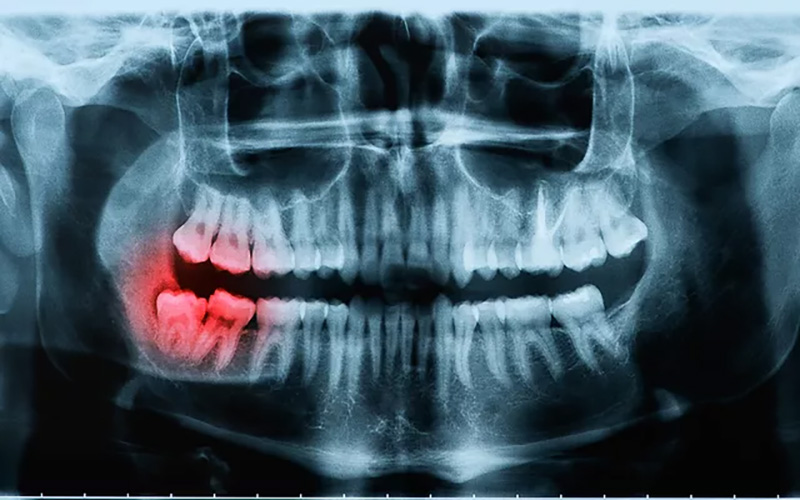

- Chụp X quang toàn cảnh: Loại chụp này hiển thị tất cả các răng và các cấu trúc xương xung quanh. Nó giúp chẩn đoán sâu răng, u nang, áp xe, ảnh hưởng của răng và các bệnh nướu răng một cách chính xác nhất.